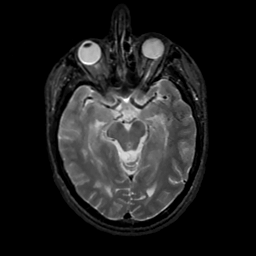

MR Study #7, March 24, 1991 -- Slice #20